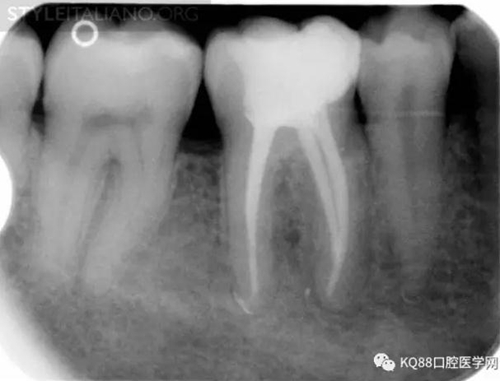

Img. 3 - The frequency of post-endodontic pain is higher in teeth with periapical or periradicular lesions. Infected debris can be forced in the periradicular tissue through a resorpted apex, thus generating acute inflammation. Creating a glide path prior to instrumentation and using a step-down technique can reduce the amount of extruded debris.

Img. 4 - Case 2: This necrotic first mandibular molar was treated in one visit, and the patient complained of post-operative pain. Analgesics and antibiotics were prescribed, and occlusion relieved. Symptoms disappeared after two days, and a radiographic follow-up after two years showed healing of the periradicular lesion.